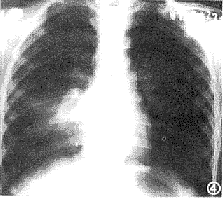

3、X線檢查多表現為單側病變,約占80%以上,大多數在下葉,有時僅為肺門陰影增重,多數呈不整齊雲霧狀肺浸潤,從肺門向外延至肺野,尤以兩肺下葉為常見,少數為大葉性實變影。可見肺不張。往往一處消散而他處有新的浸潤發生。有時呈雙側瀰漫網狀或結節樣浸潤陰影或間質性肺炎表現,而不伴有肺段或肺葉實變。體徵輕微而胸片陰影顯著,是本病病特徵之一。

X線檢查:肺部病變表現多樣化,早期間質性肺炎,肺部顯示紋理增加及網織狀陰影,後發展為斑點片狀或均勻的模糊陰影,近肺門較深,下葉較多。約半數為單葉或單肺段分布,有時浸潤廣泛、有實變。兒童可見肺門淋巴結腫大。少數病例有少量胸腔積液。肺炎常在2~3周內消散,偶有延長至4~6周者。

支原體肺炎患者胸部X線檢查變化很大,病變可很輕微,也可很廣泛。體徵輕微而胸片陰影顯著,是本病特徵之一。血常規檢查白細胞高低不一,大多正常,有時偏高。